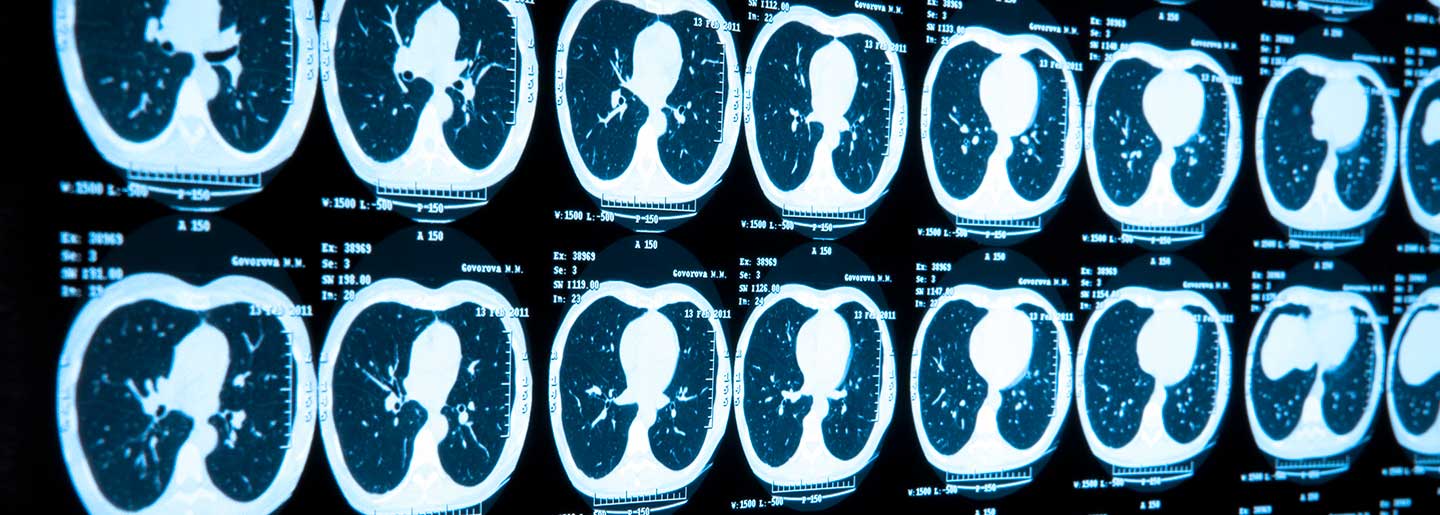

TAMPA, Fla. — Lung cancer is the leading cause of cancer death among men and women in the United States, regardless of ethnicity. Non-small cell lung cancer is the most common form of the disease, accounting for 84% of all diagnoses. One option for this group of patients is targeted therapy, a type of treatment that attacks specific genes and proteins within a cancer cell. Moffitt Cancer Center is part of a multinational, early phase clinical trial evaluating a new targeted therapy for patients with metastatic or unresectable non-small cell lung cancer who have a specific genetic mutation: EGFR Ex20Ins.

Mutations in the epidermal growth factor receptor (EGFR) gene are the most common targetable genomic drivers of non-small cell lung cancer. The role of EGFR is to help cells grow and divide. However, when EGFR is mutated, cell growth goes unchecked, allowing abnormal cells the opportunity to grow and multiply. There are several types of EGFR mutations. One type, EGFR exon 20 insertion (EGFR Ex20Ins), is seen in less than 10% of patients, but those with this specific EGFR mutation have poorer outcomes and don’t respond to FDA-approved targeted therapies, such as tyrosine kinase inhibitors. In addition, therapies are needed for patients whose tumors progress on experimental inhibitors for EGFR Ex20Ins.